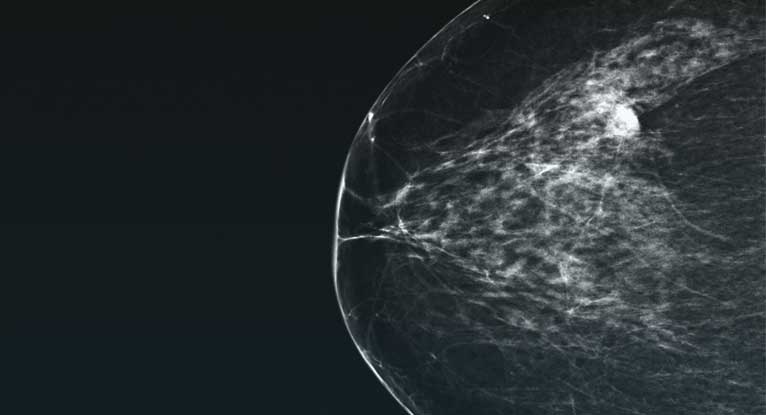

Breast tomosynthesis cost image This image representes breast tomosynthesis cost.

Tomosynthesis is an imaging or X-ray technique that can be used to screen for early signs of breast cancer in women with no symptoms. This type of imaging can also be used as a diagnostic tool for women that are having breast cancer symptoms. Tomosynthesis is an advanced type of mammography.